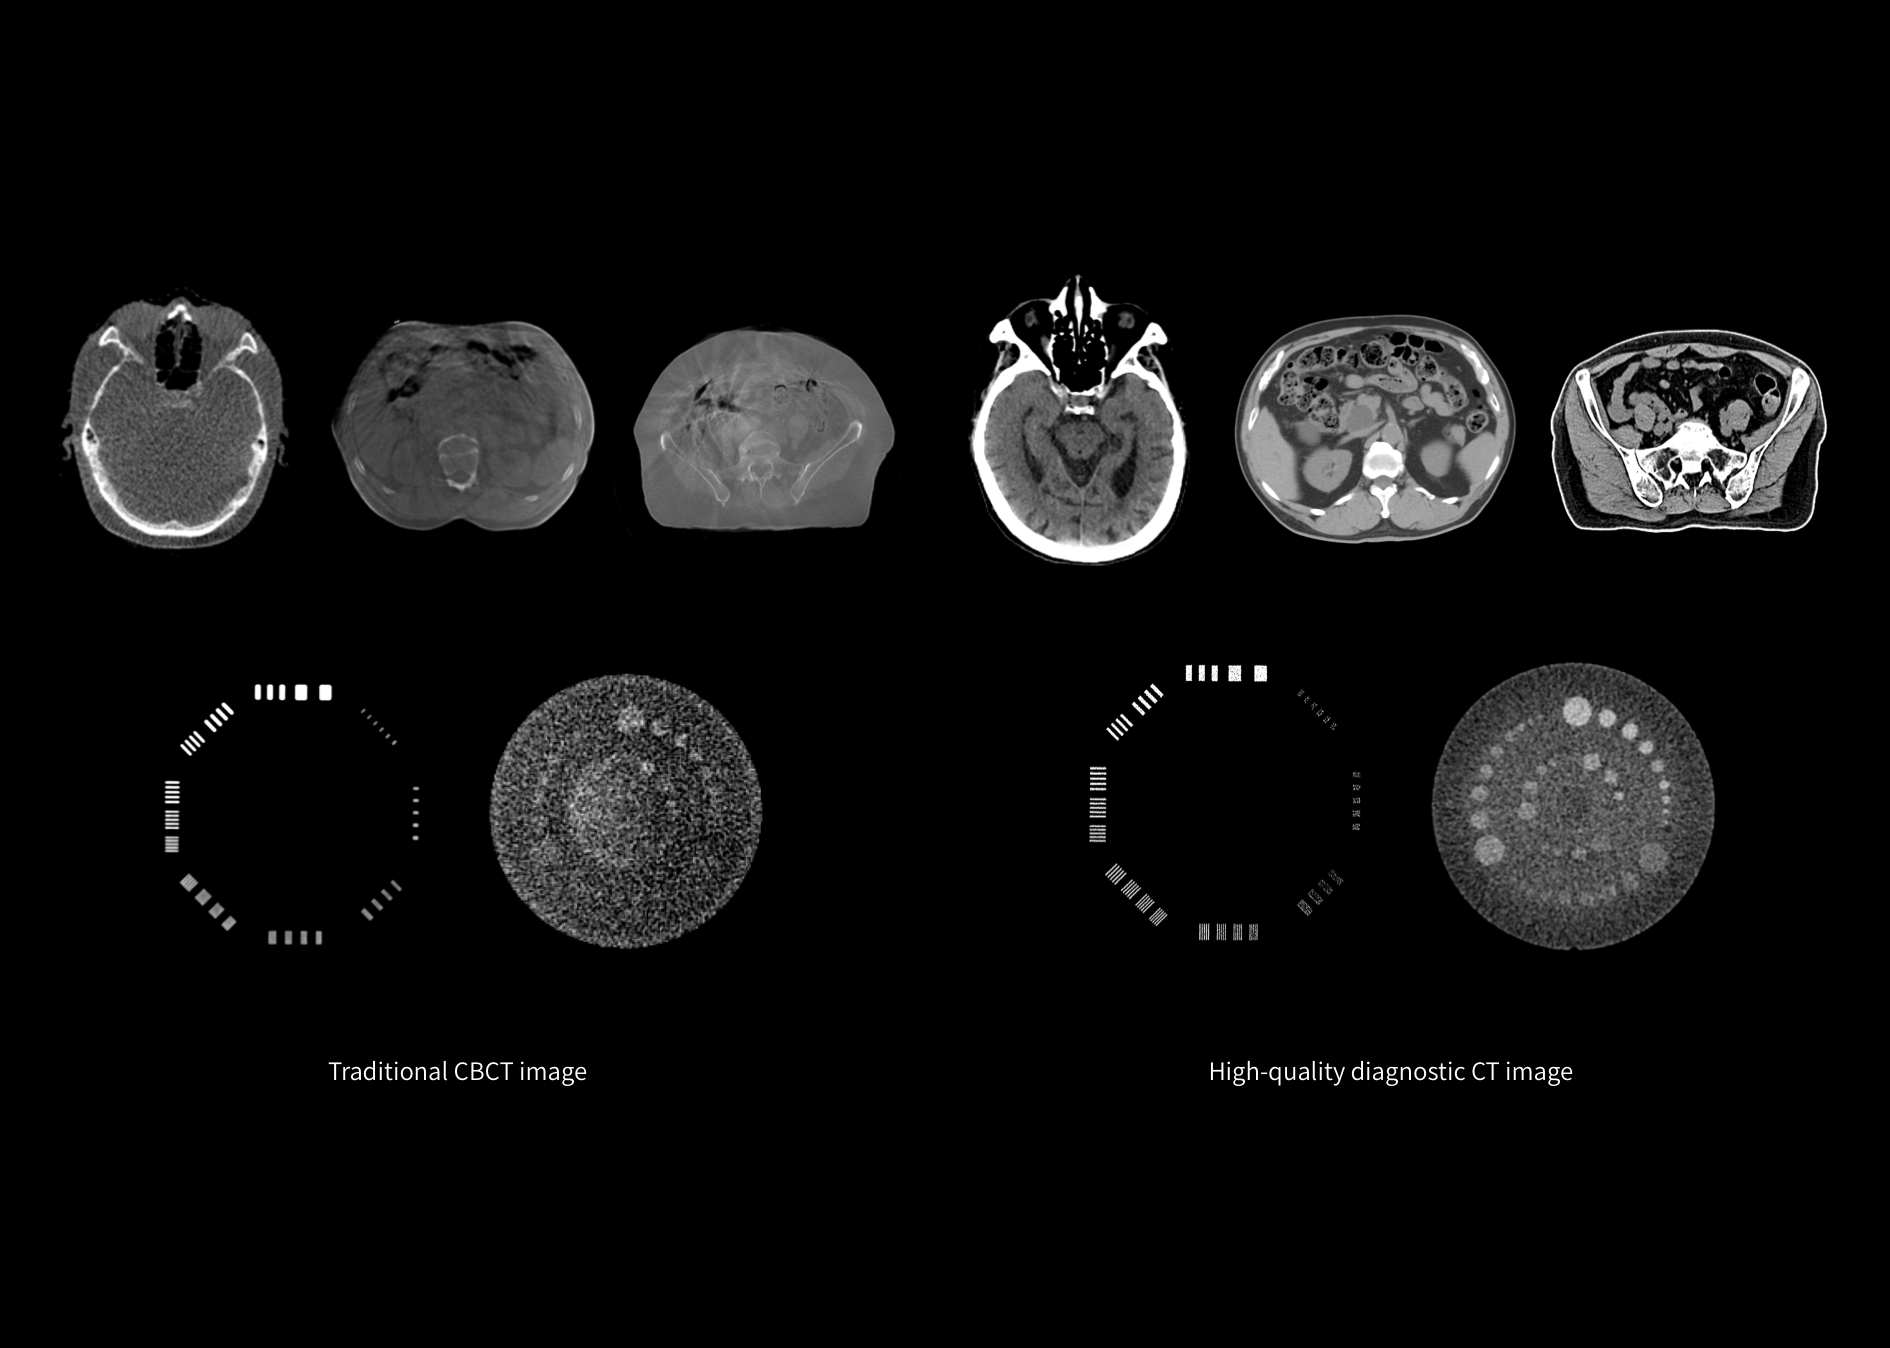

Noua generație de radioterapie personalizată și de înaltă precizie este posibilă datorită utilizării tehnologiei IGRT (Image-Guided Radiotherapy), bazată pe imagistică CT de calitate diagnostică. Acest sistem revoluționar introduce un flux clinic modern pentru radioterapie, oferind tratamente mai eficiente, sigure și adaptate fiecărui pacient.

Alinierea coaxială a tomografului computerizat (CT) de diagnostic cu acceleratorul liniar, utilizând o masă comună, permite un tratament extrem de precis. Sistemul susține întregul flux de lucru în radioterapie — de la simularea CT și ghidarea imagistică până la administrarea tratamentului propriu-zis — asigurând continuitate, precizie și eficiență clinică ridicată.

Arhitectura digitală a sistemului, împreună cu un unghi extins al gantry-ului de 544°, o rată de doză de 1400 MU/min și un colimator multi-lamelar (MLC) dinamic cu 120 de lamele de înaltă rezoluție, permit o precizie excepțională în administrarea tratamentului. Calculul dozei se realizează prin algoritmul avansat Monte Carlo, care asigură o distribuție optimă a radiației și protejarea țesuturilor sănătoase din jurul zonei țintă.